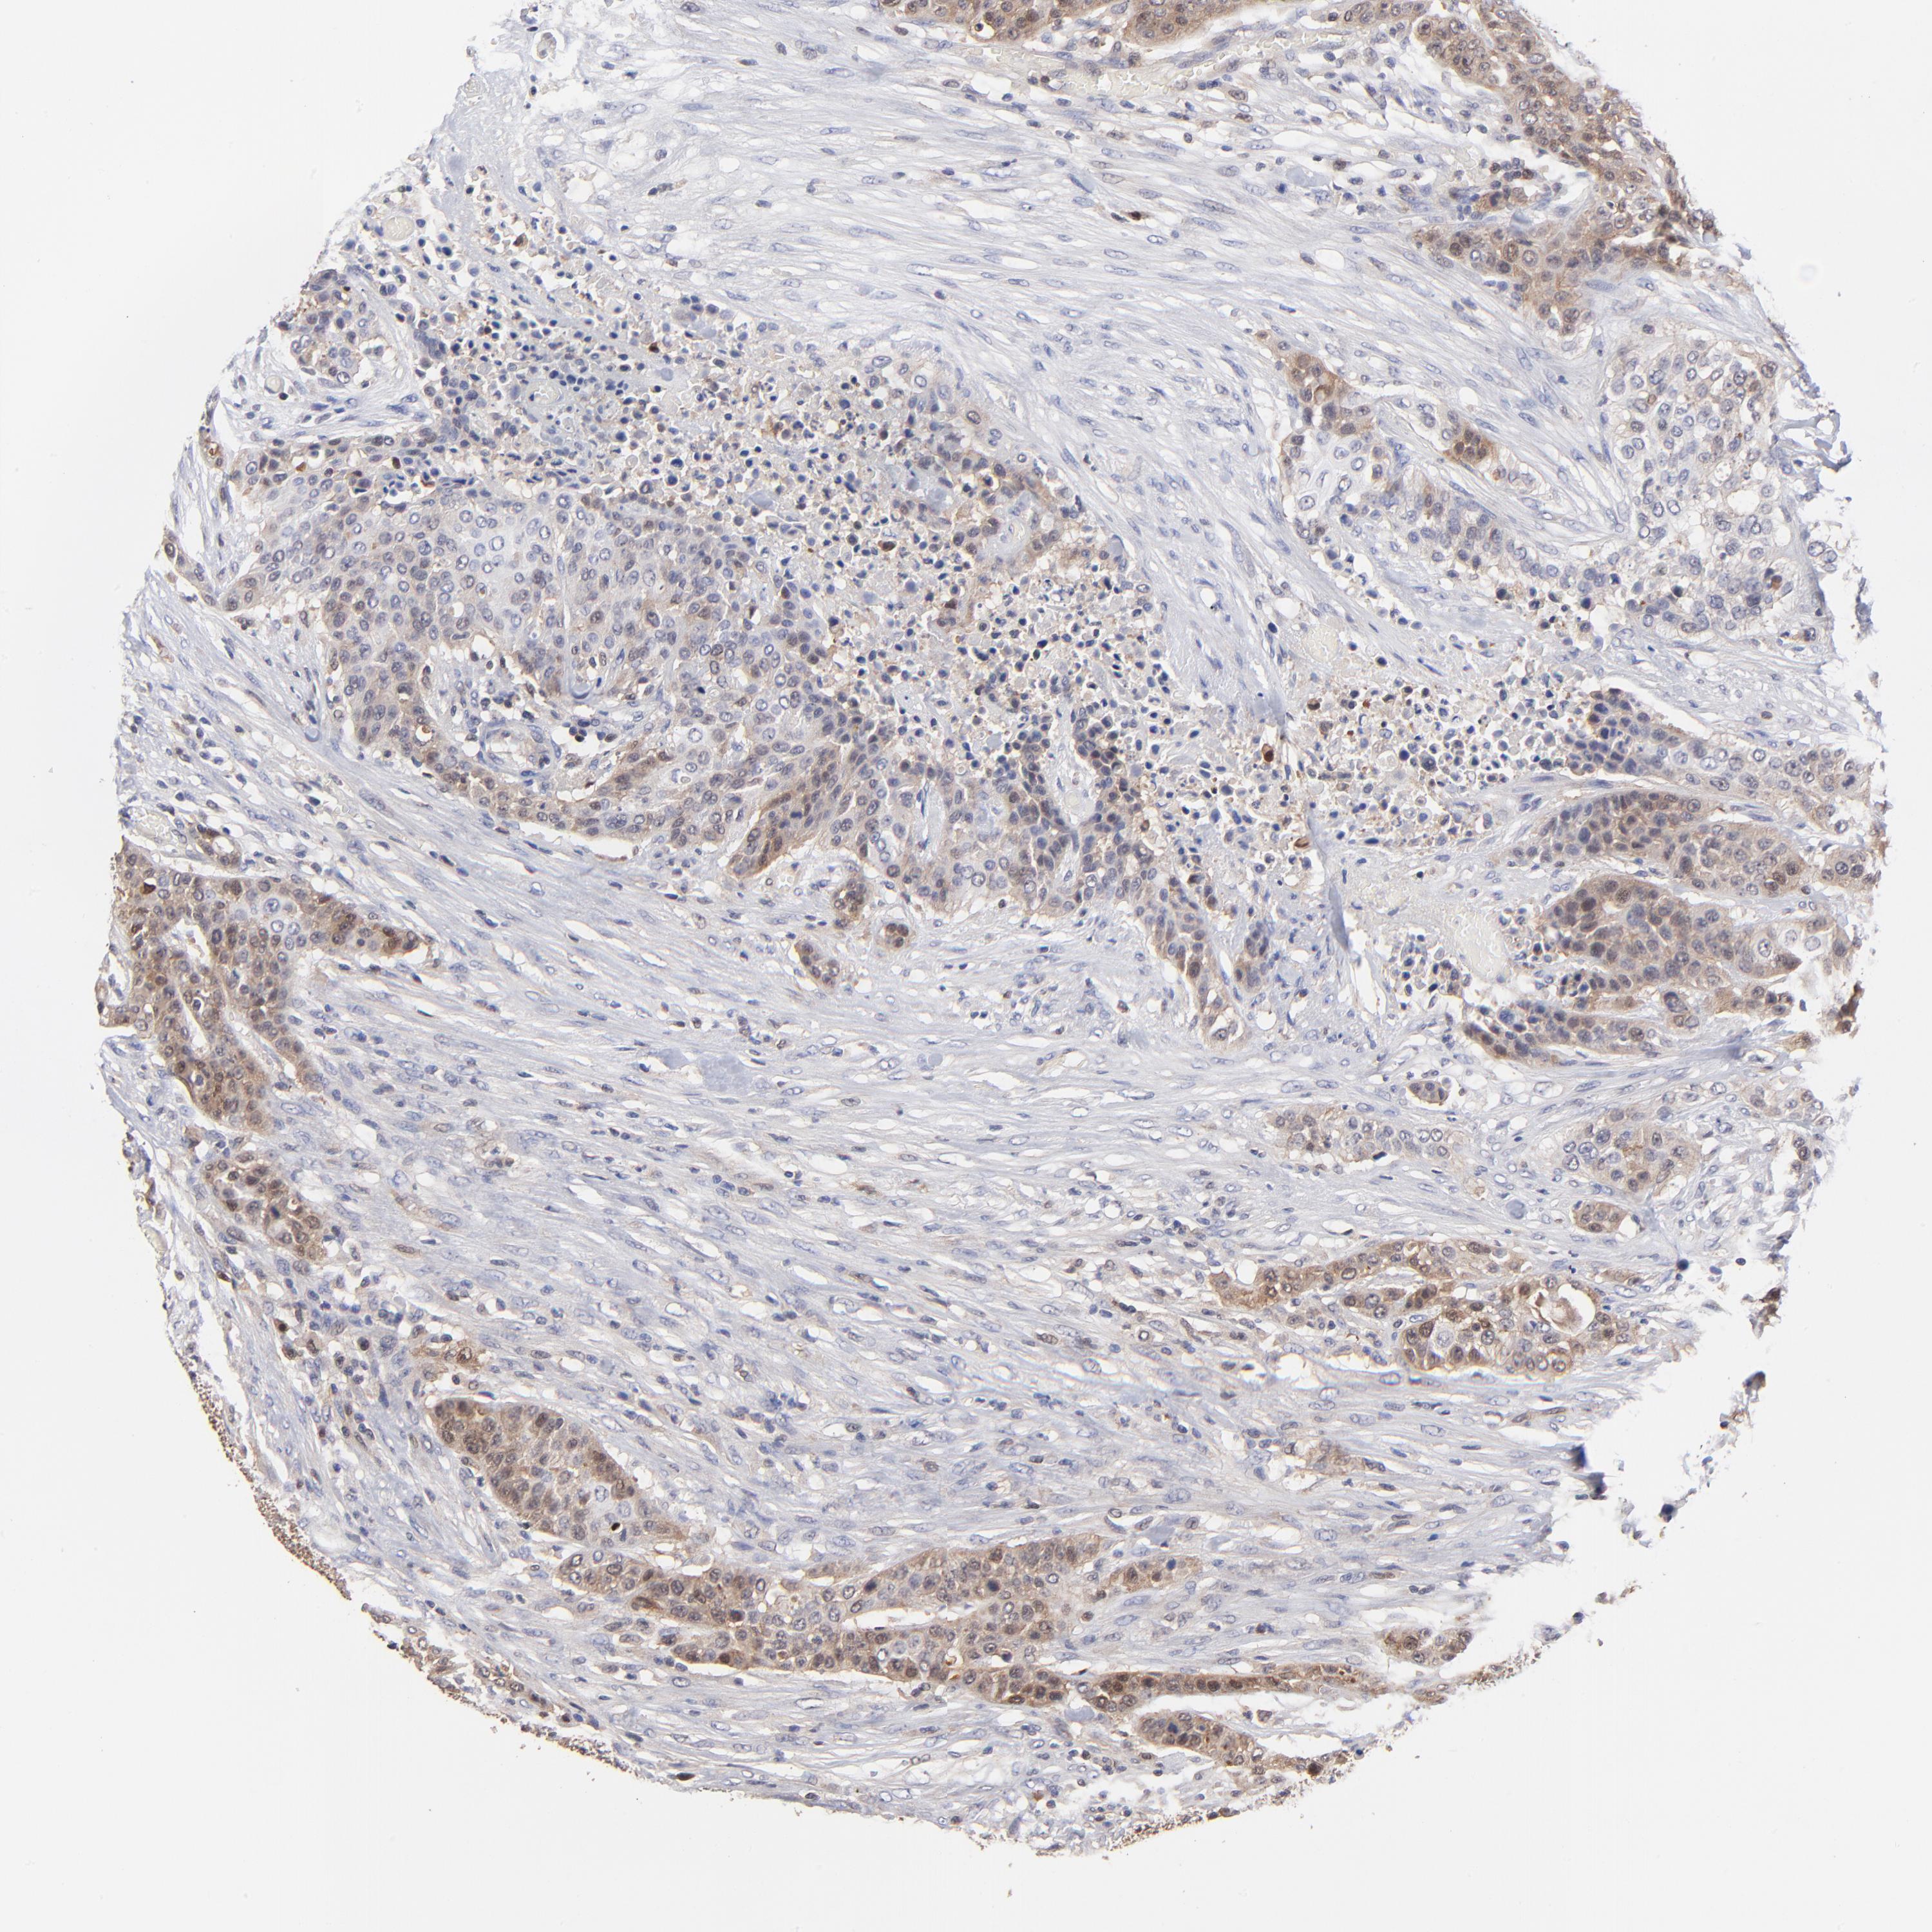

UROTHELIAL CANCER - Protein expressioni

A mouse-over function shows sample information and annotation data. Click on an image to view it in a full screen mode. Samples can be filtered based on level of antibody staining by selecting one or several of the following categories: high, medium, low and not detected. The assay and annotation is described here.

Note that samples used for immunohistochemistry by the Human Protein Atlas do not correspond to samples in the TCGA dataset.

Antibody stainingi

Antibody staining in the annotated cell types in the current human tissue is reported as not detected, low, medium, or high, based on conventional immunohistochemistry profiling in selected tissues. This score is based on the combination of the staining intensity and fraction of stained cells.

Each image is clickable and will lead to virtual microscopy that enables deeper exploration of all samples and also displays staining intensity scores, fraction scores and subcellular localization as well as patient and tissue information for each sample.

Antibody HPA002832

Staining

High

Medium

Low

Not detected

Intensity

Strong

Moderate

Weak

Negative

Quantity

>75%

75%-25%

<25%

None

Location

Nuclear

Cytoplasmic/membranous

Cytoplasmic/membranous,nuclear

Urothelial carcinoma, Low grade